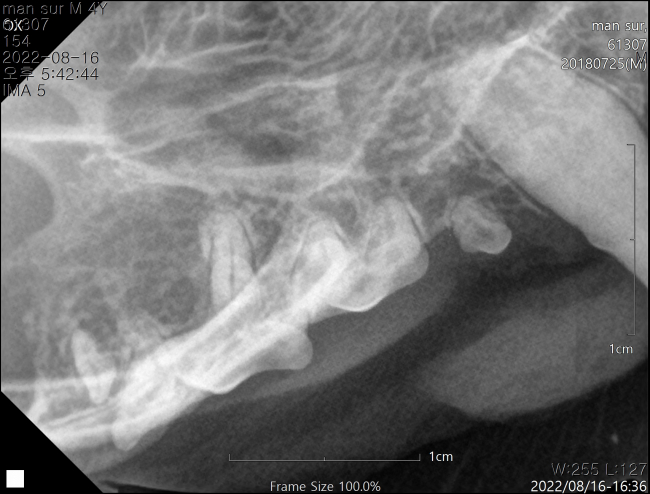

치료전 대상묘

치료중 대상묘